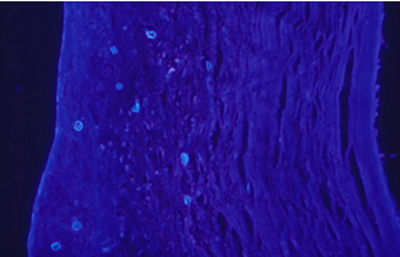

Blanco de Calcofluor

El uso del fluorocromo Blanco de Calcofluor no es excluyente de otras coloraciones, pues al ser en base acuosa no es permanente y la preparación puede lavarse en agua corriente para luego ser coloreadas con Giemsa, PAS u otras coloraciones, con el fin de reconfirmar los hallazgos microscópicos y volverlas permanentes para guardarlas.

Blanco de Calcofluor: Sobre el porta-objetos con el extendido ya fijado colocar unas gotas de Blanco de Calcofluor al 0.1% y de Azul de Evans 0.1%. Esperar 3 minutos. Cubrirlo con un cubre-objetos. Retirar con papel de filtro el exceso de líquido que se exterioriza por los bordes del cubre-objetos. Examen en el microscópio de fluorescencia. Emplear filtro excitador de 365 nm. y de emisión de 450-490 nm. Algunos autores favorecen emplear un filtro de emisión con longitud de onda más larga, fuera de la banda azul, en 520-550 nm. si bien con estas longitudes de onda la visualización de la emisión fluorescente es menos intensa.

Las imágenes de Acanthamoebas muestran una cápsula circular u ondulada, refringente de color azulado o verde manzana, notablemente más intensa que los materiales y tejidos que la rodean. Suelen medir de 12 a 16 µm de diámetro. El contenido del quiste es azul tenue. (Figura 37 , 38, 39 y 40)

Acanthamoeba CW, Original x160

Fig. 39 CW, Original x160